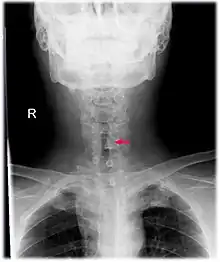

Neck AP x-ray of patient with post-intubation subglottic stenosis, as shown by the narrowing in the tracheal lumen marked by the arrow.